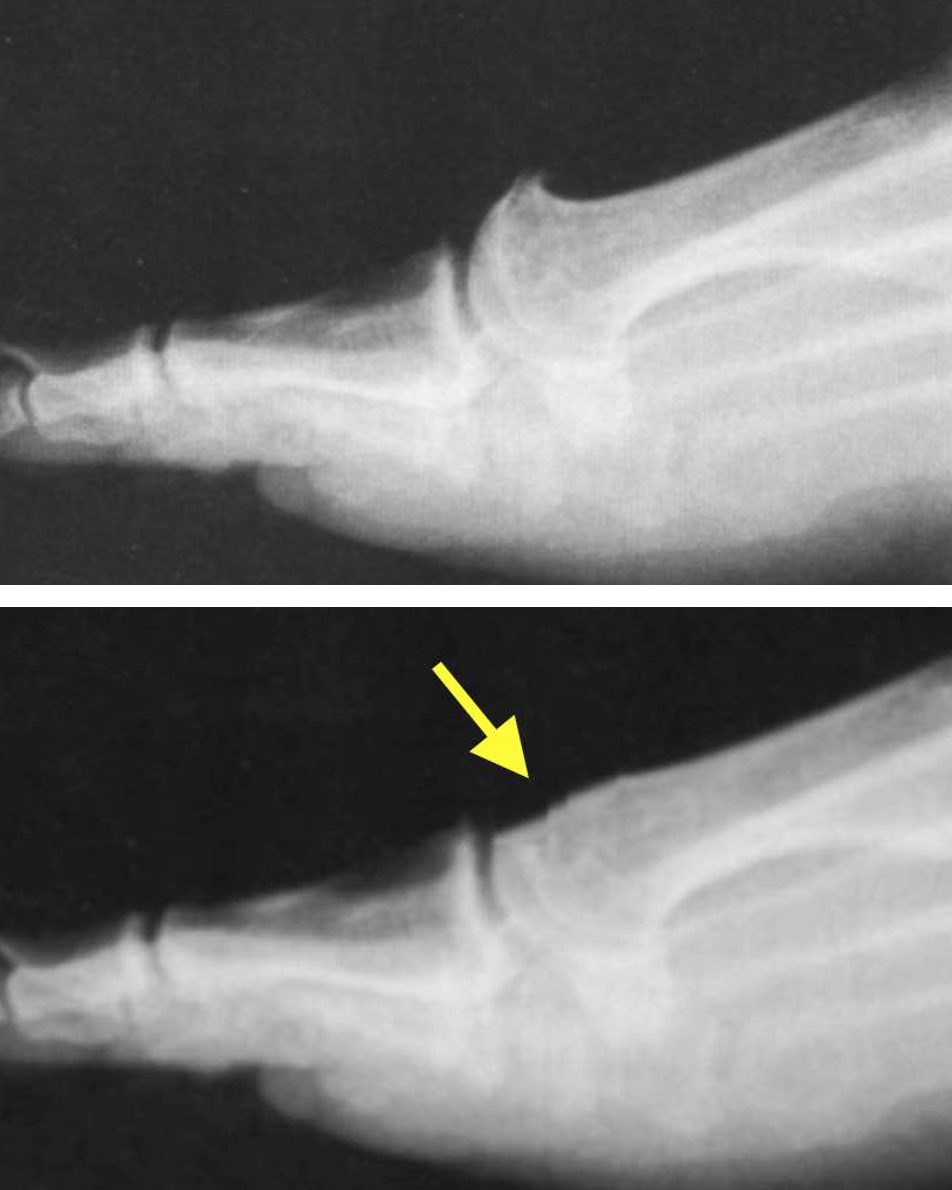

A

Cheilectomy is performed if mainly the upper part of the big toe joint is

involved. The upper part of the joint is trimmed and the joint washed out.

At the same time as a Cheilectomy, the bone in the base of your great toe may be re-aligned to make the most of the movement you have left in the joint (Moberg’s Osteotomy).